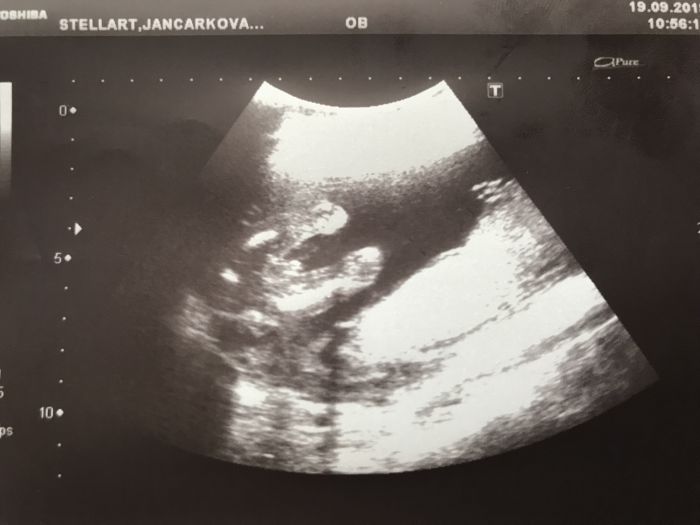

Ahoj všichni, včera jsem byla na druhém screeningu 20+2 a mimčo vážilo jen 316 gramu, říkala, že je vše v pořádku (plus mínus dva týdny nikdo prý neřeší).. jsem koukala, že holky na začátku 21.tt mají i okolo 400 gramů. Tak jsem se lekla trochu.

Nika a kolik měří? Já jsem podle mého gynekologa dne 19+6, dle kalkulačky na netu 20+0 a dle genetického centra a velikosti plodu jsem 20+3. Takže je vše opradu různé. a vážíme 340g, tak to není takový rozdíl.

Ahoj holky, já jsem byla na screeningu ve 21+2 a malá vážila 377g, takže to máme všechny tak podobně